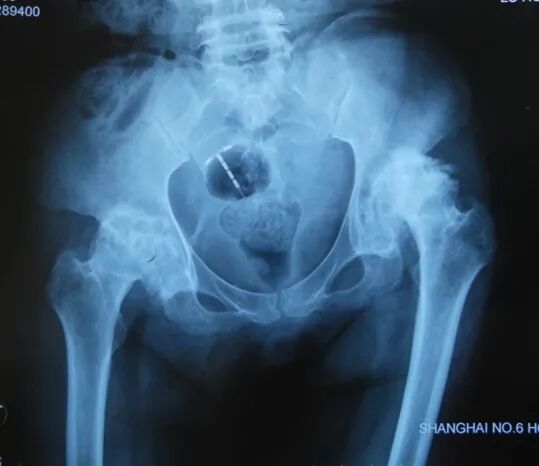

如何恢复offset及双下肢等长术前评估及模板测量术中评估

-髋臼假体的旋转中心点是不是恢复正常,参考髋臼假体下缘和横韧带的关系

-股骨假体旋转中心点是否恢复正常,参考股骨头假体中心点和股骨大转子的关系

确定正常侧髋关节的旋转中心镜像至患侧:

确定股骨颈截骨线对侧髋关节正常,可以对侧为参照

-定出截骨高度(可以小粗隆为参照)

-镜像确定在患侧的截骨高度